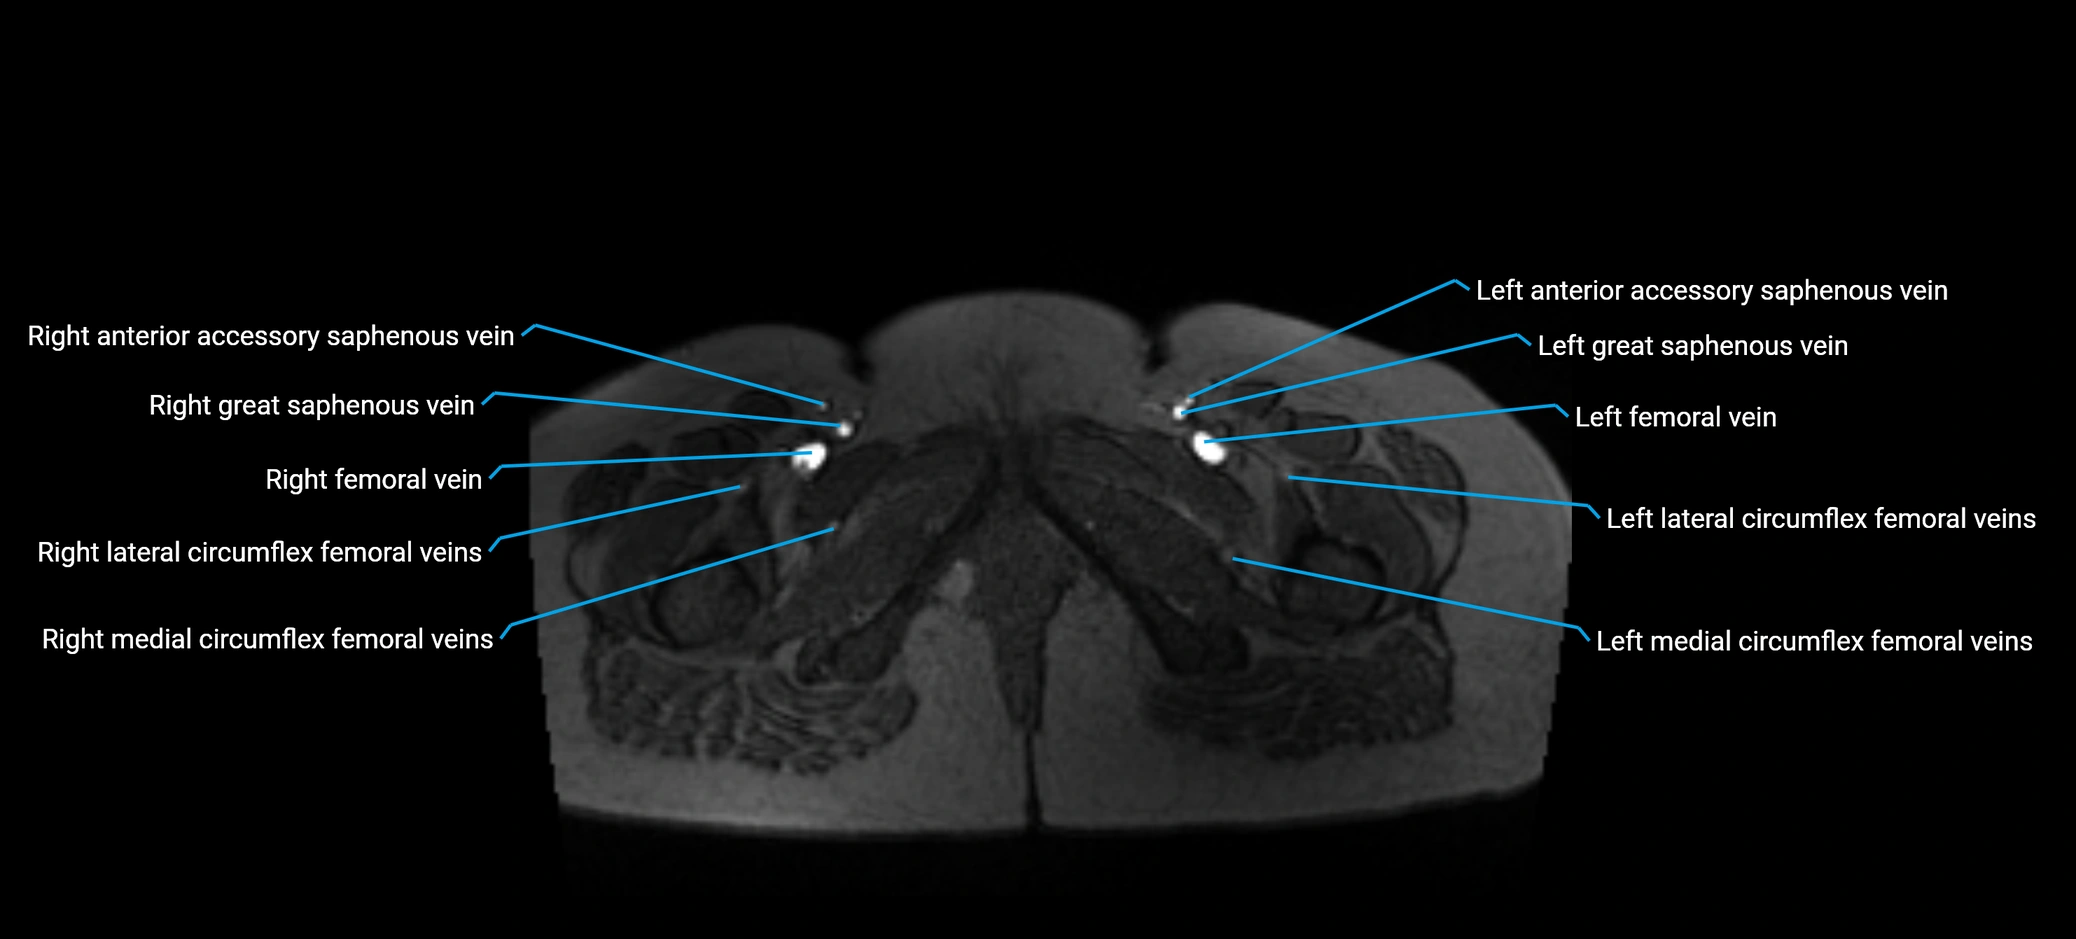

MRI image

image